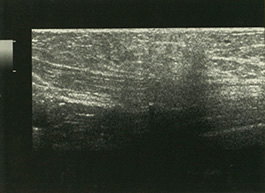

主訴は血性の乳汁分泌。拡張した乳管と約4mm程度の斑状低エコー域が区域性に分布してみられた(矢印)。細胞診では悪性が疑われ、部分切除を行った。断端陰性だった。 |